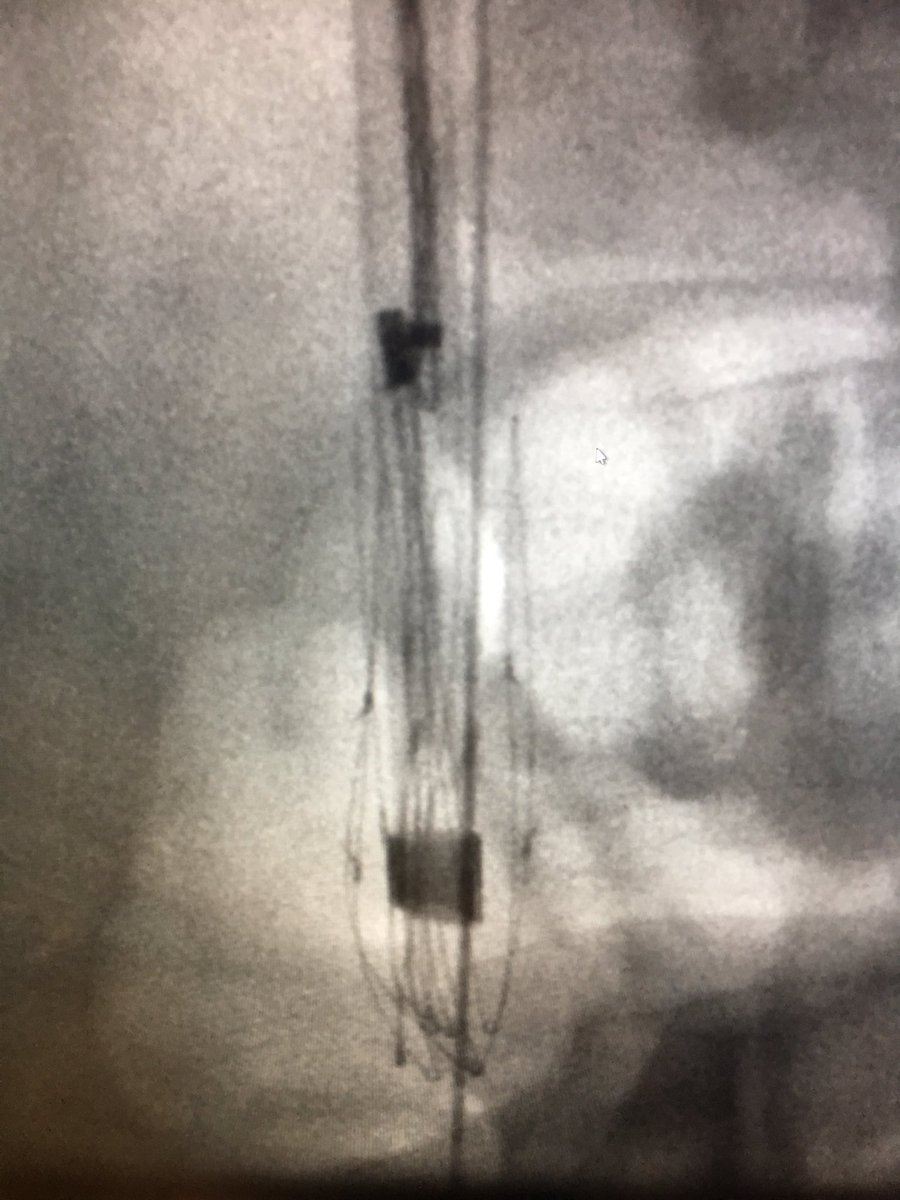

Filter Out Friday fun w/ @arslanmd @jtass6 @roshah31 5yr old embedded Venatech!! #laserlife #GTFO @rkryu @kush_r_desai @IvcFilterClinic